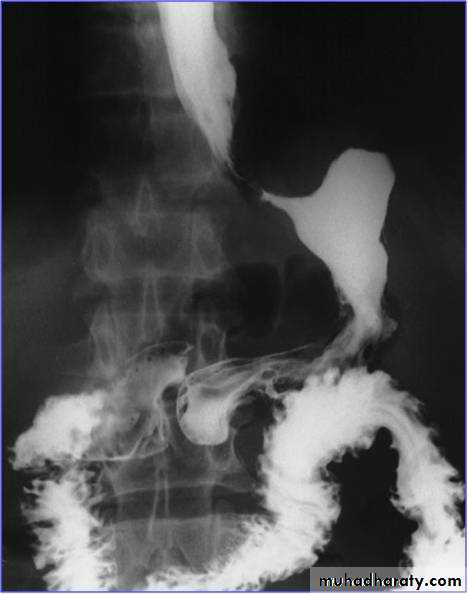

Barium meal: is a poor alternative.

The underlying cause is usually a scirrhous adenocarcinoma with diffuse submucosal infiltration, leading to thickening and rigidity to the stomach wallLocation: 50% in the antrum, 20-30% occur in the gastric body, 20% in the cardia, or diffuse submucosal infiltration (uncommon).

Linitis plastica